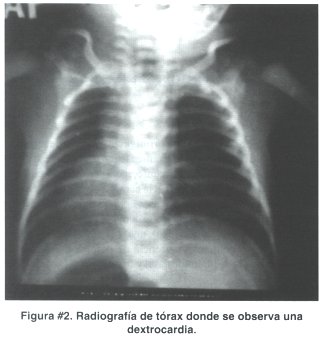

Dentro de los exámenes de gabinete destacó la radiografía de tórax que mostró dextrocardia, como se puede observar en la figura # 2.

Los diagnósticos de ingreso a la sala de neonatología fueron: recién nacido a termino pequeño para la edad gestacional con un retardo del crecimiento intrauterino y malformaciones múltiples compatibles con ciclopía y dextrocardia. La evolución fue mala y el paciente falleció a la hora de vida.